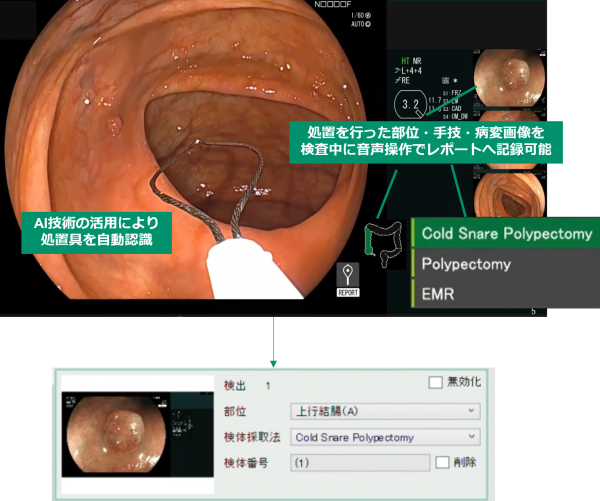

1.処置情報記録機能

AI技術の活用により、検査中の画面内で処置具を自動認識し、採取した検体番号と直前に撮影した静止画像を紐づけて保存する。さらに医師が部位情報、手技を発声するとそれらの情報も紐づけることができる。検査後レポート作成時に、医師は保存された処置情報を確認し、レポートへ反映すべき内容を確定する。レポート作成のために医師が処置情報を記憶するストレス、看護師がメモを取る手間の軽減に貢献する。

AI技術の活用による処置具の自動認識と、医師の音声操作による部位・手技の登録により、1回の処置に紐づけて病変画像、部位、手技、検体番号を検査中に記録することができる。医師による確認の後、これらの記録がレポートへ反映される。

「部位名」、「手技名」をそれぞれ音声入力することで、検査中に処置の情報を記録することができる。